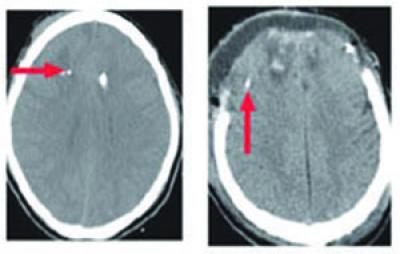

These are CT scans of two patients with traumatic brain injury. Red arrows point to the catheter tips used to collect samples of brain fluid by microdialysis. Though both patients are injured, only the CT scan on the right shows an obvious problem (top of image). While CT scans are good at finding problems that are immediately life-threatening (such as a hemorrhage that requires surgery), they do not always reflect the amount of axonal injury. Measuring tau protein by microdialysis and special imaging techniques, such as diffusion tensor imaging, may help to better assess the extent of injury to the brain's fragile axons.